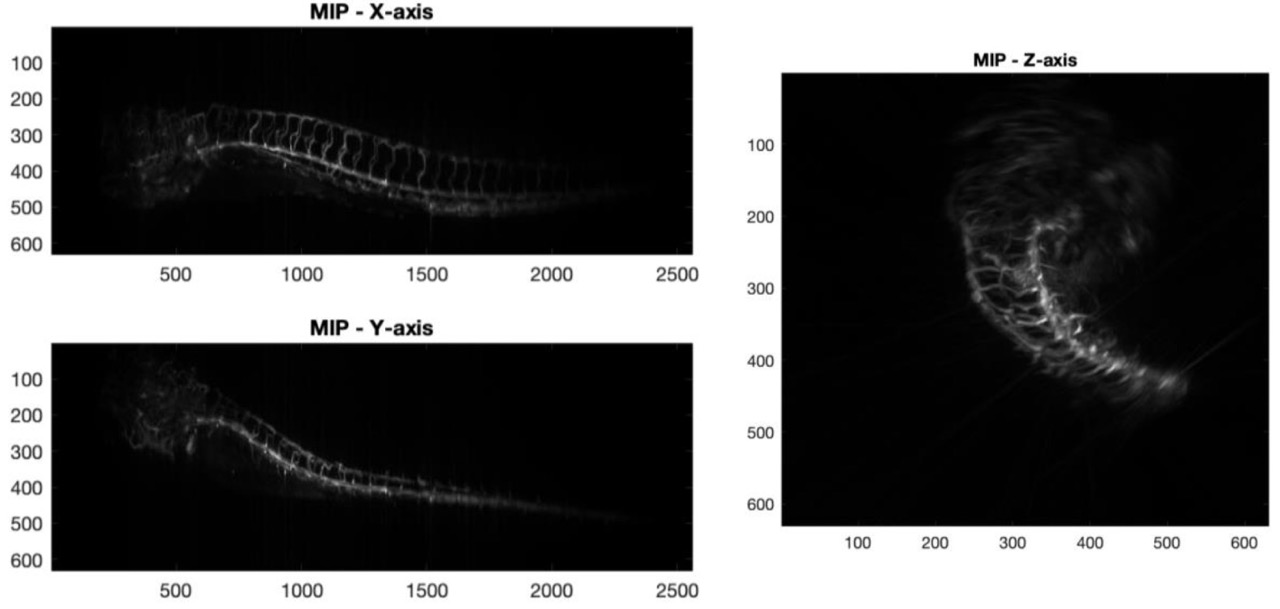

- Maximum Intensity Projection (MIP): Implemented orthogonal MIP projections along the x, y, and z axes to highlight internal structure without segmentation.

- Interpretability: Demonstrated how projection-based rendering supports rapid insight in biomedical imaging contexts.

✅ Applied scientific visualisation techniques to enhance interpretability of 3D biomedical volumes, supporting both qualitative and quantitative analysis.